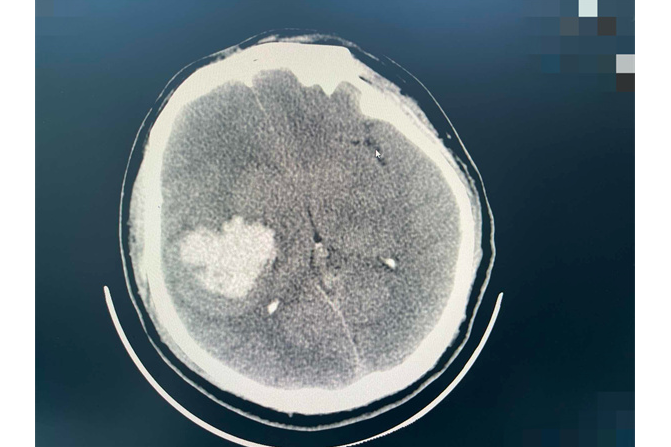

时间回到7月31日清晨,家住海宁市许村镇的小龙(化名)像往常一样上完厕所,突然发现左侧肢体像被无形的重物绑住,任凭他怎么用力,都无法正常活动。家人察觉异常后,紧急呼叫120将他送往海宁市中心医院急诊。急诊CT检查结果很快出来,右侧基底节-颞叶出血,出血量已超过70毫升,结合小龙既往高血压病史(平日监测血压偏高但未规范治疗),急诊测舒张压达181-200mmHg,考虑为高血压性脑出血,且出血仍在持续!

手术前的影像